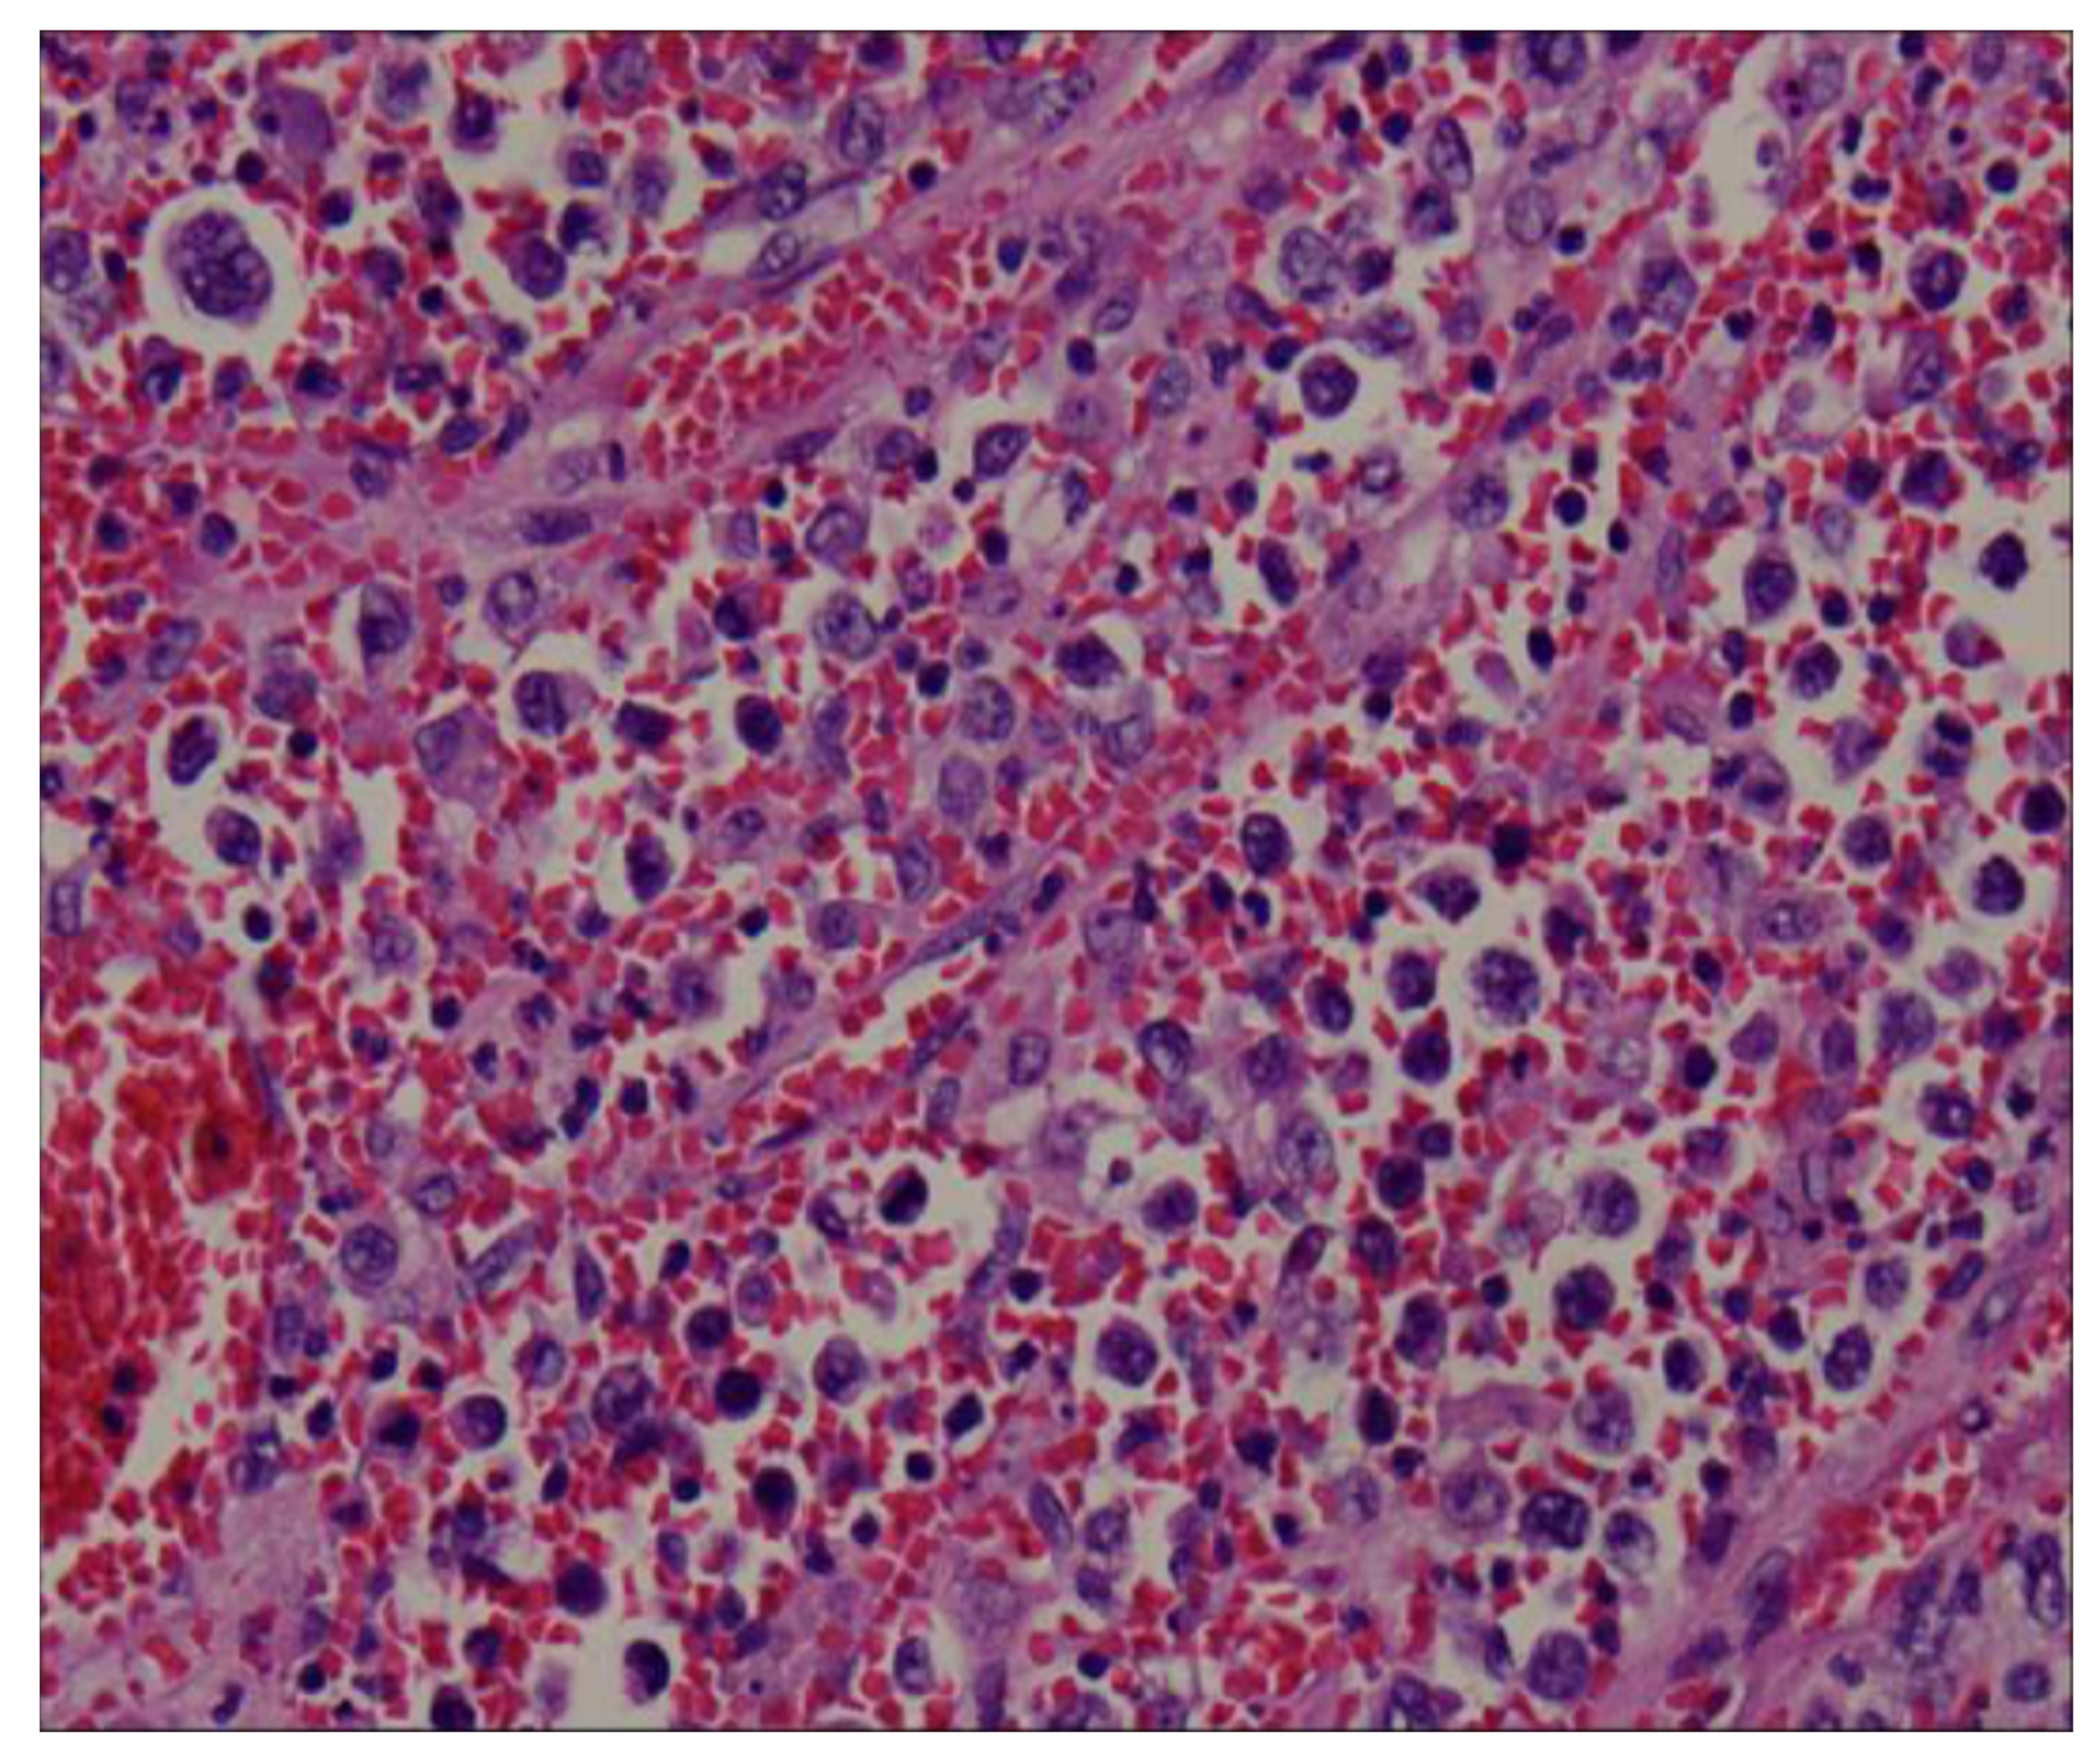

The splenectomy operation removed a large solid splenic tumor. The histology exhibited a diffuse proliferation of a monotonous population of large neoplastic lymphoid cells and extensive necrosis (Figure 4). Immunohistochemical testing revealed a positive result for CD20, CD79a, BCL6, and BCL2, and a Ki-67 index greater than 90% (Figure 5). Immunohistochemical testing was also negative for CD3 and CD10. The patient was discharged without complications 1 week later. A subsequent bone marrow examination and positron emission tomography–computed tomography scan were negative. A diagnosis of primary splenic diffuse large B-cell lymphoma was recorded. The patient received CHOP regimen chemotherapy. The patient was asymptomatic upon follow-up examination and exhibited no recurrence 6 months after chemotherapy.

Figure 4.

The histology revealed a diffuse proliferation of a monotonous population of large neoplastic lymphoid cells and extensive necrosis.